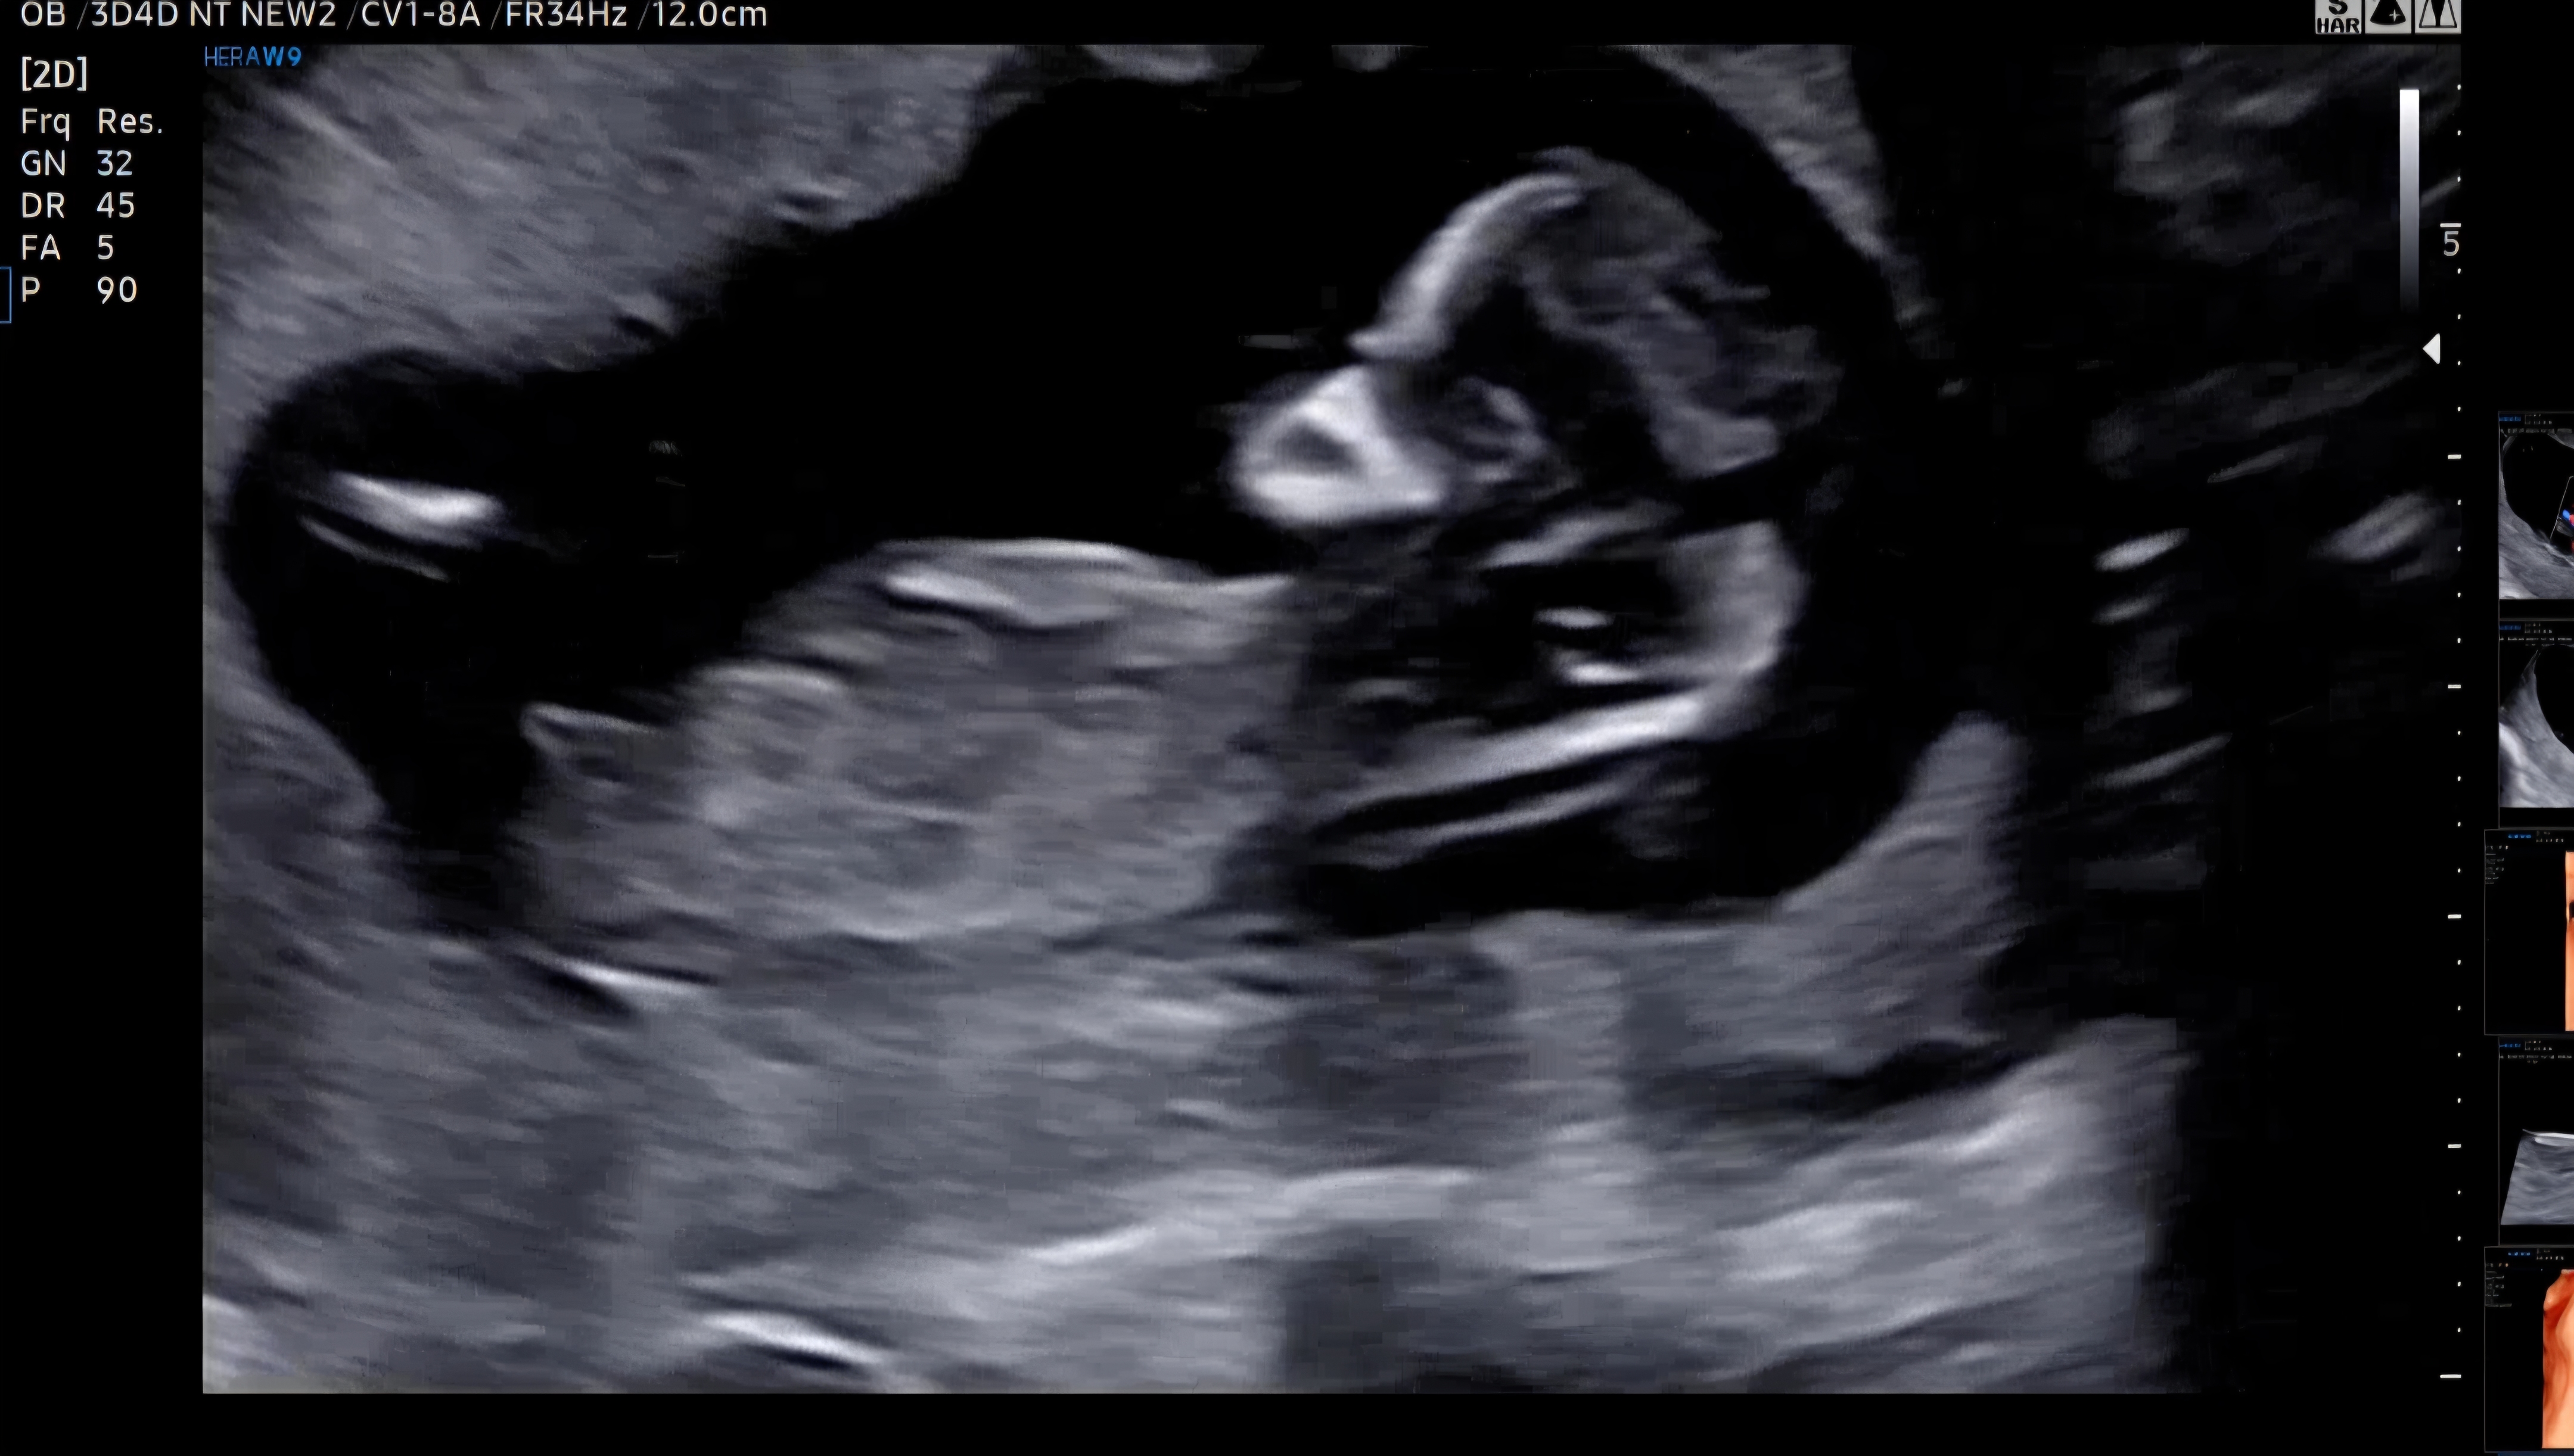

12주1일차 초음파 입니다! 딸일까요, 아들일까요???? 참견 마구마구 부탁드려요🙏